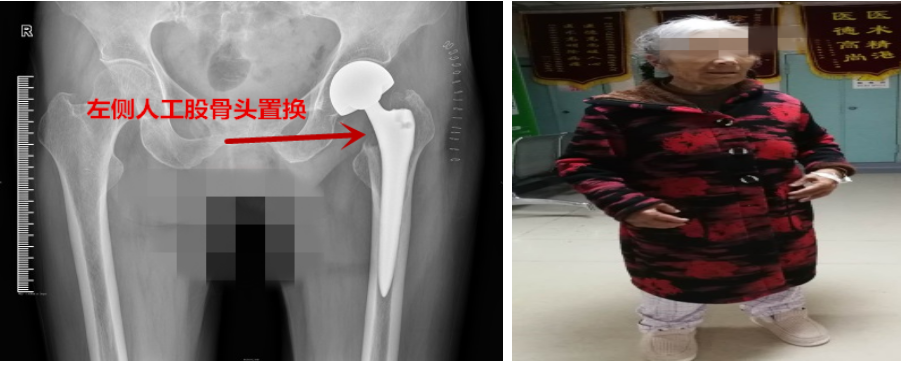

患者术前X片

2月中旬,虽正值新冠肺炎疫情防控特殊时期,对人员流动管理严格,但为了让患者尽快治愈,骨科通过州人民医院院士工作站,邀请到成都市第一人民医院关节组主任医师李程,通过多方协调和准备,李程医生经过多重疫情防控筛查卡点来到州人民医院。2月17日,患者术前准备就绪,麻醉科主任雍记智主任亦为患者完善了术前访视,经副院长杨林、医务科科长蒲光军等全力支持,2月18日骨科顺利为患者在全麻下进行了“左侧人工股骨头置换术+滑膜切除术+软组织松解术”。